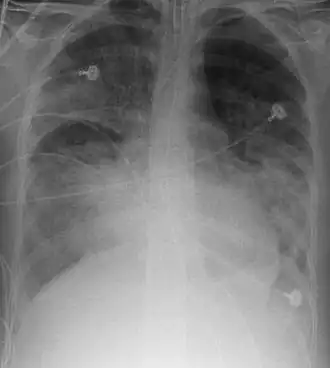

Рентгенограмма органов грудной клетки пациента с ОРДС

При рентгенографии лёгких видны двусторонние диффузные инфильтраты, иногда — плевральный выпот. Такие признаки неспецифичны и также характерны для кардиогенного отёка лёгких, что затрудняет дифференциальную диагностику[15][16]. Компьютерная томография показывает негомогенную инфильтрацию лёгких в определённых отделах (в задненижних отделах у лежачих больных)[17]. Это объясняется зависимым от силы тяжести распределением отёка лёгких и сдавлением вышележащими отёчными отделами лёгких[18].